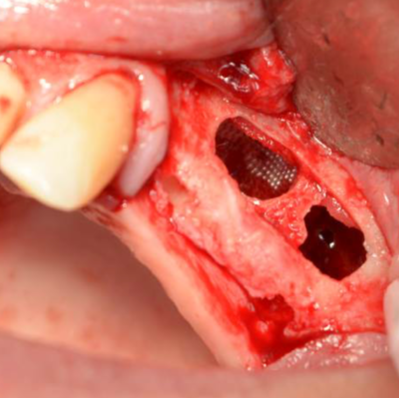

- Schließen des Osteotomiefensters zum Sinuslift

- Knochenblutung

- Sicherung der Schneider-Membran, auch als Perforationsversorgung

- Schließen des Osteotomiefensters nach Wurzelresektion